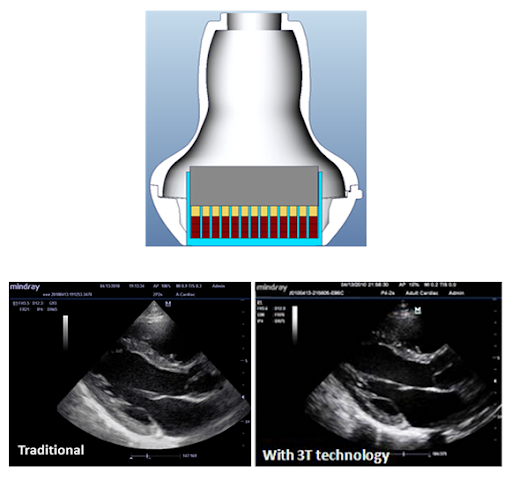

3T Технология производства датчиков

Запатентованная компанией Mindray технология датчиков, обеспечивающая расширение диапазона частот и повышение эффективности передачи изображений.

Тройная структура согласующего слоя обеспечивает повышенную чувствительность, более широкий диапазон частот и улучшенное соотношение «сигнал/шум»

Применение полностью разделенных кристаллов для снижения перекрестных помех, улучшения фокусировки и повышения поперечного разрешения.

Терморегулирование для лучшей передачи звуковой волны